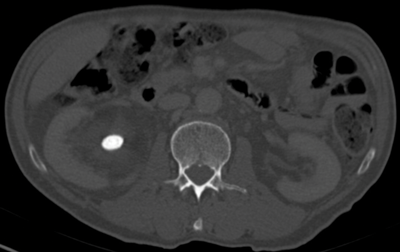

Figure 2a: Abdominal windows stone with contrast.

Figure 2b: Bone windows stone with contrast.

CT urograms can be performed with a pre-contrast CTKUB to assess for stone disease and calcification, but some centres only perform a post-contrast urographic phase in order to decrease radiation dose. Newer dual-energy CT scanners include software that enables a ‘virtual pre-contrast CT’ to be reconstructed by a subtraction technique. Using bone windows enables some calculi to be visualised even in the presence of contrast in the collecting systems due to the different HU values of contrast and calculi (Figure 2). However, it can be difficult to clearly depict some calculi using abdominal windows in this group of patients as the stone will be masked by the excreted contrast.